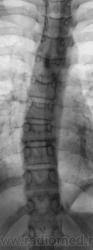

Пациент направлен на рентгенографию ОГК по поводу виража.

Как трактовать изменения в грудном отделе позвоночника, как сколиоз или как сколиотическую осанку?

Хотелось бы попросить опытных рентгенологов, которым часто приходится сталкиваться с ВВК, показать на данных снимках торсию и ротацию.

... и, чтобы было удобнее - снимки с увеличением.

[[wysiwyg_imageupload:257:]][[wysiwyg_imageupload:258:]][[wysiwyg_imageupload:259:]][[wysiwyg_imageupload:260:]]

Насколько я понимаю, рентгенологически торсия проявляется на фронтальном снимке смещением корней остистых отростков на высоте искривления в ВОГНУТУЮ сторону. Смещение корней ДУЖЕК говорит о ротации. Или я не прав?

!Определение величины торсии позвонков.Наиболее точно величина торсии, а также патологической ротации позвонков, т.е. величина деформации в горизонтальной плоскости может быть определена по данным компьютерной и магнитно-резонансной томогра­фии. В период становления методов транспедикулярной фиксации тяжелых сколиотических деформаций, разрабатывавшие эти методы хирурги использовали компьютерную то­мографию для определения точной формы позвонков в горизонтальной плоскости и, соответственно, величины торсии каждого позвонка, подлежащего фиксации. Однако, на современном этапе вертебрологии в практической работе определение абсолютной ве­личины торсии отдельно взятого позвонка редко имеет самостоятельное значение. Именно поэтому широкое практическое применение получили методы ориентировочной оценки торсии по переднезадней рентгенограмме позвоночника. При определении величины торсии важно помнить, что анатомическим центром позвонка и, соответственно осью, вокруг которой происходит его «скручивание», условно считается задняя продольная связка.

Pedicle-метод (от pedicle— ножка, NashС., MoeJ.H., 1969) (рис. 7, а) основан на опре­делении проекционного положения корня дуги позвонка относительно боковой поверх­ности его тела на выпуклой стороне деформации. В норме, при отсутствии торсии, корни дуг позвонка располагаются симметрично как относительно остистого отростка (проекционной его тени), так и относительно боковых сторон тела позвонка. Через сере­дину тела позвонка проводят вертикальную линию, после чего половину позвонка на вы­пуклой стороне дуги условно делят на 3 равные части. При I степени торсии отмечается только асимметрия контуров корней дуг при их обычном расположении в пределах на­ружной трети. При II и III степени торсии корень дуги проецируется соответственно на среднюю и медиальную треть, а при IV — на контралатеральную половину тела позвонка,

Хм, судя по вышеоптсанному - в вышеуказанном случае максимум можно поставить 1-ю степень торсии. (корни дуг распологаются симметр чно относительно остистых отростков и боковых сторон тела, ну, может есть небольшая ассиметрия самих корней Или я чего то не так понял, или плохо смотрю :(